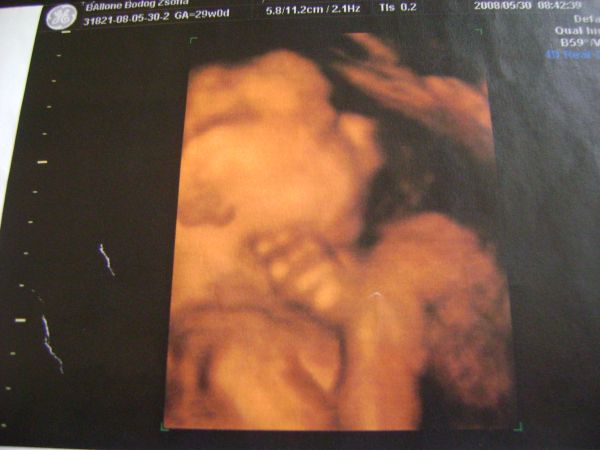

Ma voltam genetikai uh-n. Csoda volt újra látni a babát!!!

Mindene megvan, és persze mindene tökéletes! Már 52 mm magas!!! :lol:

Egy kép Róla: